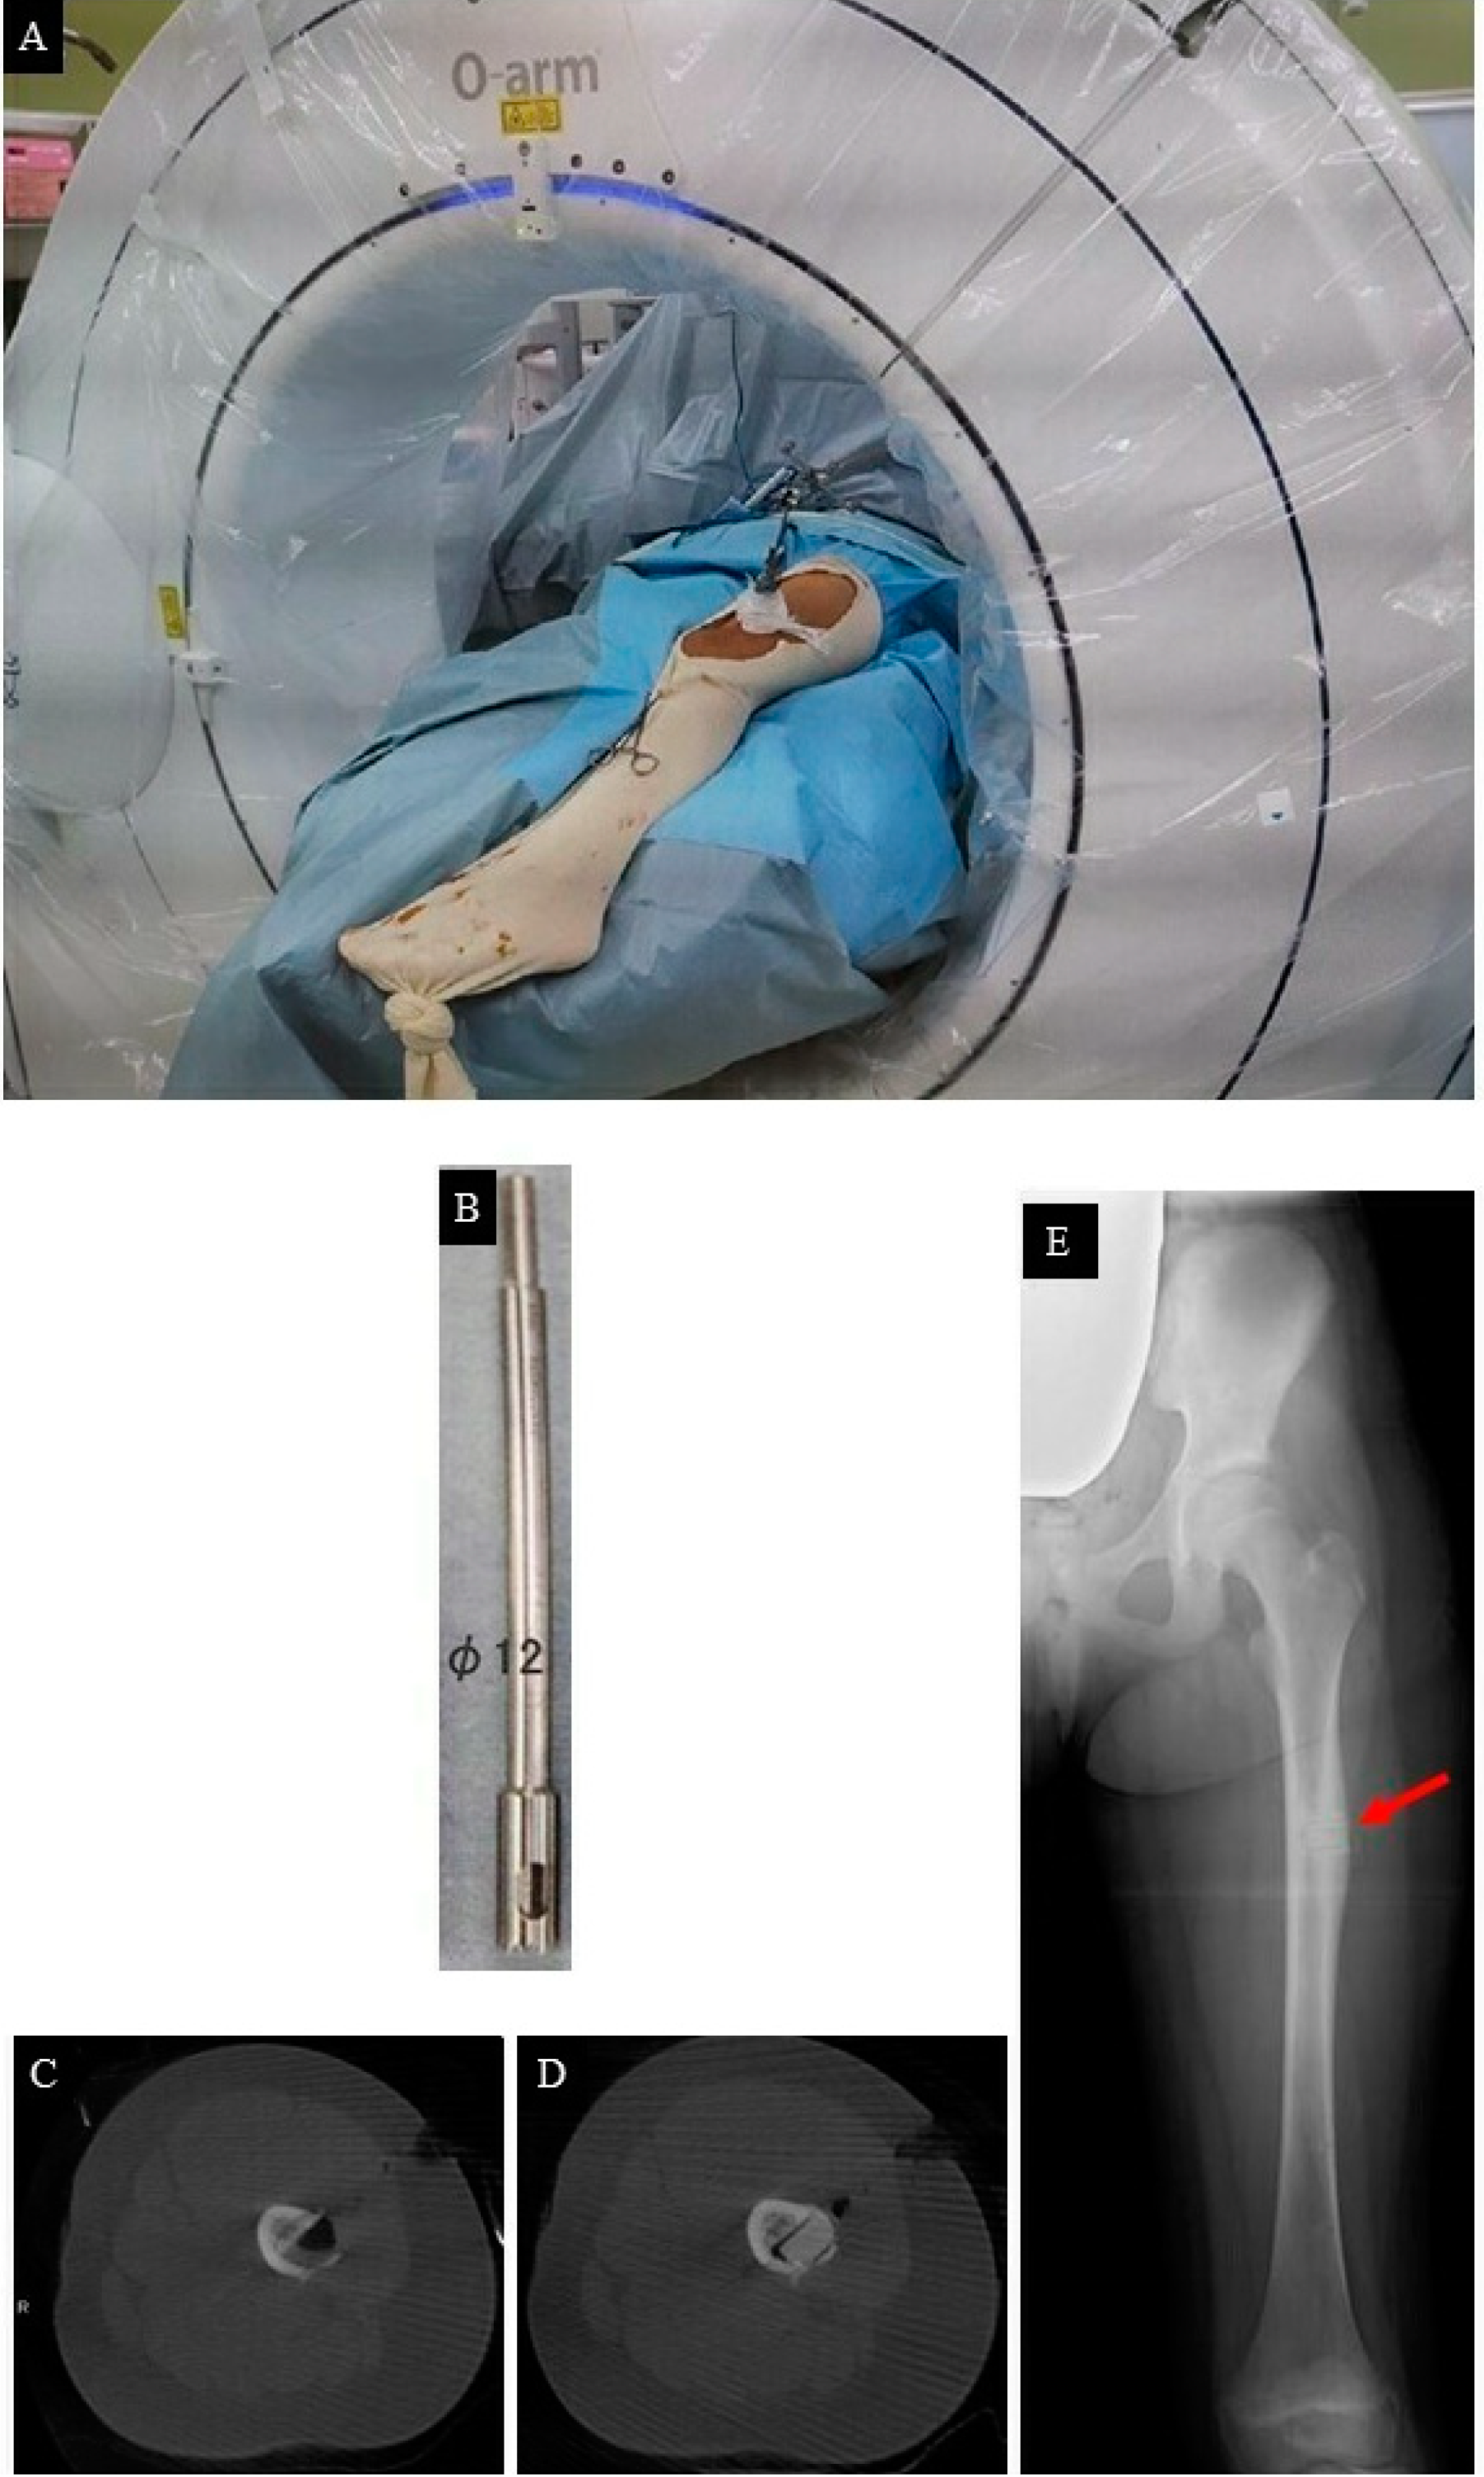

- Clinical and radiological evaluation of the osteoid osteoma.

- FEA to predict bone mechanical properties after the bone resection with the decided method, modified by tumor dimensions.

- Tumor resection and femoral stabilization, according to results of FEA.